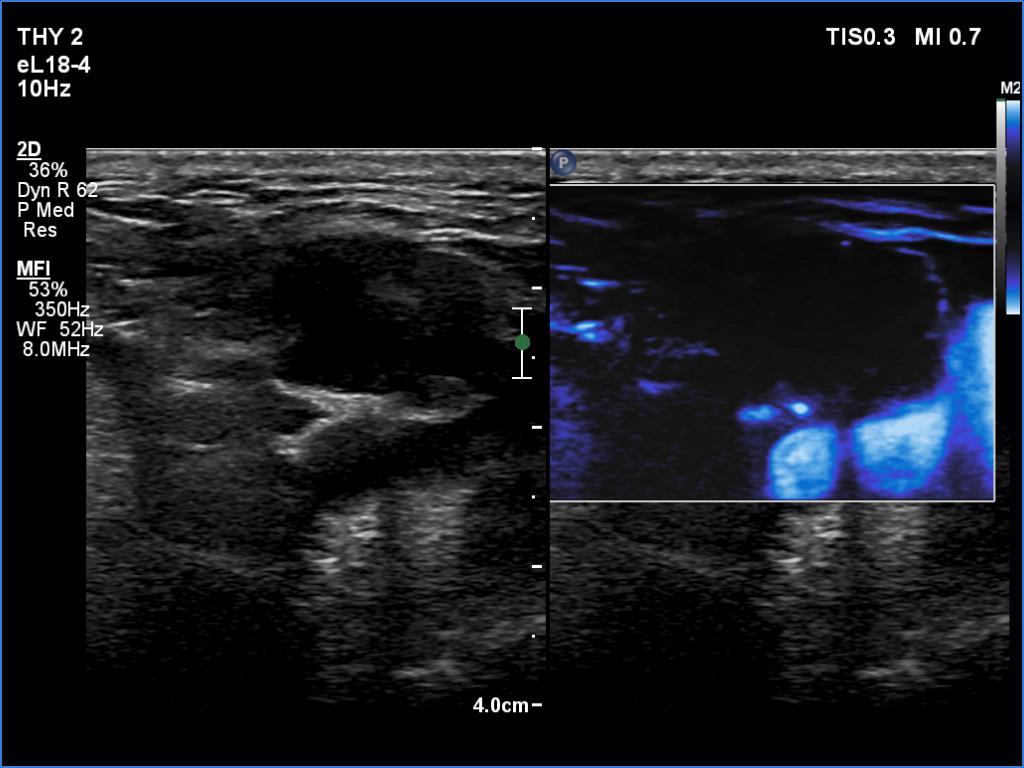

Ultrasonography. The right lobe was echonormal and intact. A large mass occupied almost the entire left lobe. On this side, normal thyroid tissue could only be identified in the dorsal part. The mass was composed of echonormal and hypoechoic areas, had macrocalcifications, irregular intranodular vascularity and proved to be very hard on elastography. There were multiple lymph nodes in III, IV and V left neck compartments. One of the nodes was in close proximity to the jugular vein and was suspicious of having broken into the vessel. The trachea was significantly narrowed at the lower level of the thyroid.

2. There are several remarkable findings in this case, e.g., the destruction of the left lobe by the tumor, the elastography pattern, the relation of the largest metastatic lymph node and the jugular vein, the ultrasound demonstration of the trachea' stricture.